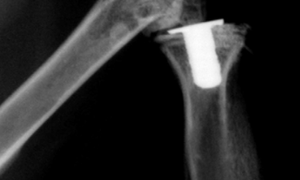

大動物肩または上腕の激しい打撲、溝や柵を乱暴にとびこす、車の荷台からとびおりる、交通事故などが原因となります。若馬では、はじめて勒をつけて調教を開始した時に、興奮し棒立ちになってから倒れた時に発生することが多い。子牛、若牛では四肢の骨折の1...